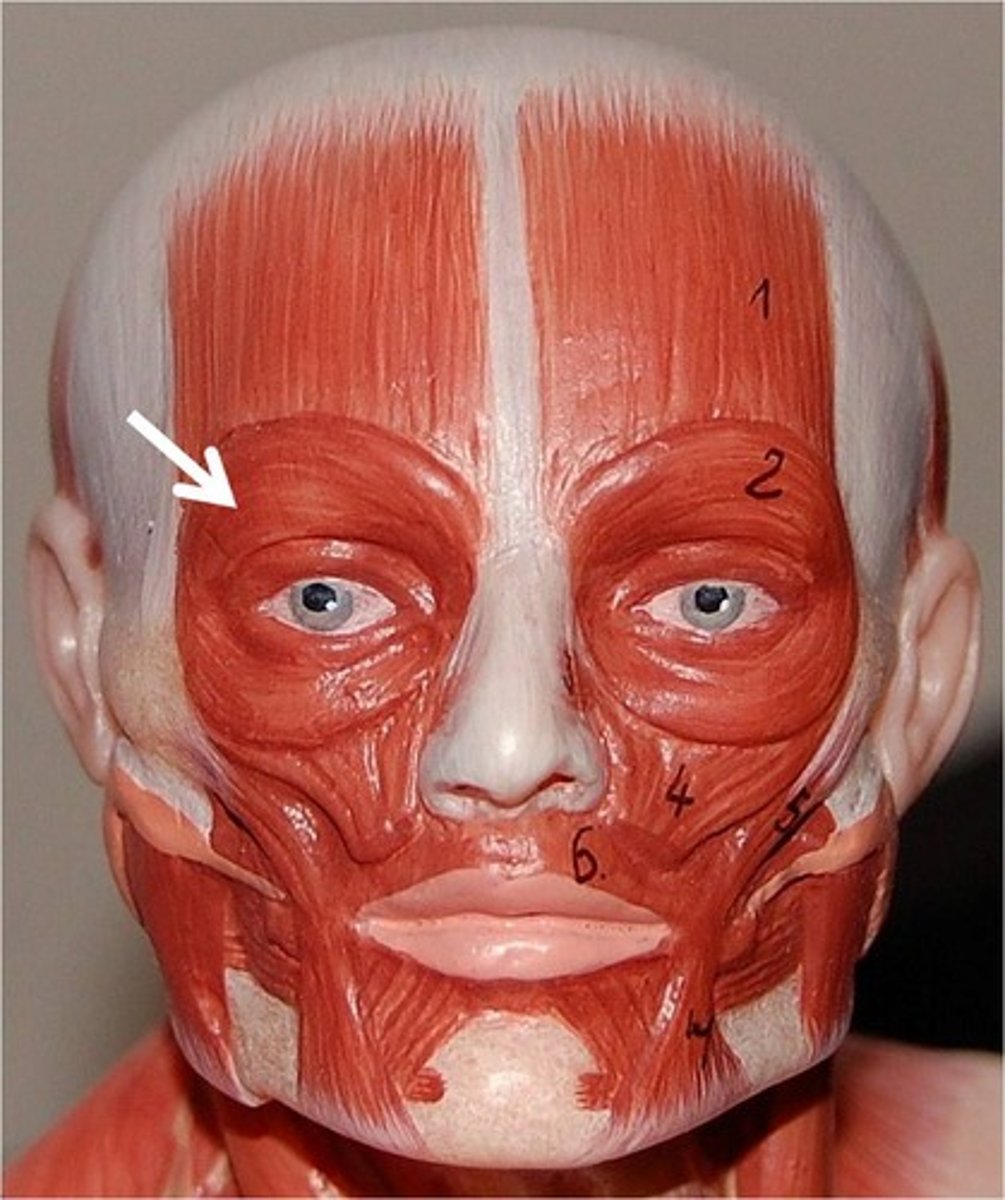

orbicularis oculi muscle

muscle around the eye that closes the eyelids